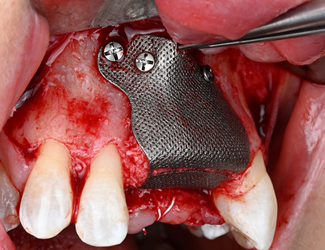

Yngre kvinne som mistet tenner 11-22 gjennom traume. Både en horisontal og vertikal defekt i et estetisk utfordrende område. En Yxoss 3D-printet membran produseres gjennom planleggingsverktøyet, i dette tilfellet IO-skanning og CBCT som grunnlag. En preprotetisk voksing på den tiltenkte suprakonstruksjonen produseres for å forutsi fremtidig protese og tiltenkt beinvolum. Partikulært bein påføres membranen som deretter fikseres på plass. Etter 6 måneders helbredelse fjernes membranen. Regenerert bein uten pseudoperiosteum er påvist, implantater kan plasseres med gode marginer og god protesetilstand.

Yxoss membran fylt med partikkelformet autologt bein og Geistlich Bio-Oss.

Bendefekt klinisk

Fast Yxoss membran